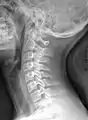

مهرههای گردنی

مهرههای گردنی به مجموعهای از مهرههای گردن گفته میشود که بیرون از جمجمه قرار دارد. غیر از پستانداران مهرهای گردنی، همانند مهرههای سینهای دارای دنده میباشند.

اندازهٔ این مهرهها معمولاً از دیگر مهرهها کوچکتر است و دارای سوراخ در زوائد عرضی خود میباشند. در مهرههای دیگر این سوراخها در زوائد عرضی موجود نمیباشد و این امر این مهرهها را از سایر مهرهها متمایز میسازد.